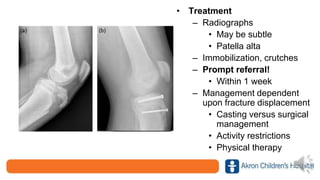

• Treatment

– Radiographs

• May be subtle

• Patella alta

– Immobilization, crutches

– Prompt referral!

• Within 1 week

– Management dependent

upon fracture displacement

• Casting versus surgical

management

• Activity restrictions

• Physical therapy

• Treatment – Radiographs •May be subtle • Patella alta – Immobilization, crutches – Prompt referral! • Within 1 week – Management dependent upon fracture displacement • Casting versus surgical management • Activity restrictions • Physical therapy